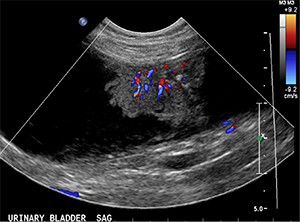

Abdominal ultrasonography results are shown below:

- At least 3 florid-like urinary bladder masses are seen in the dorsal and ventral wall. The largest measures 4.3cm x 1.5cm x 2.4cm, with pinpoint hyperechoic specks and marked vascularity on color flow Doppler. This is consistent with primary urinary bladder neoplasia, likely a transitional cell carcinoma (TCC). The proximal urethra and prostate look normal.